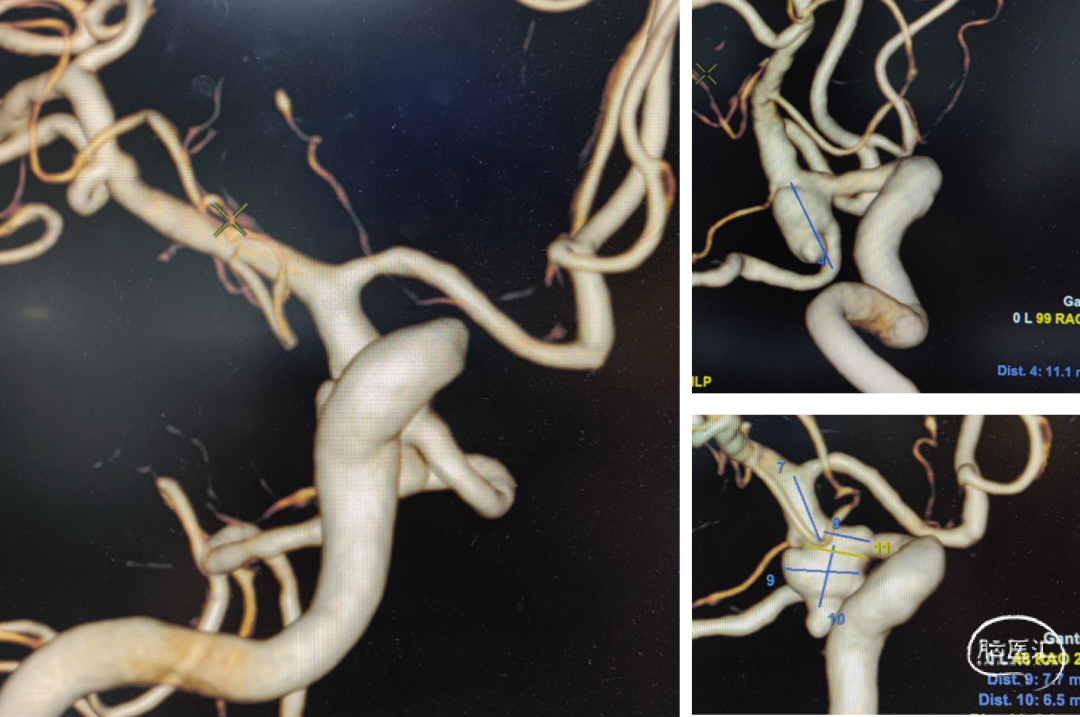

头颅CTA

支架选择

LEO3.5x25 Atlas 3.0x15